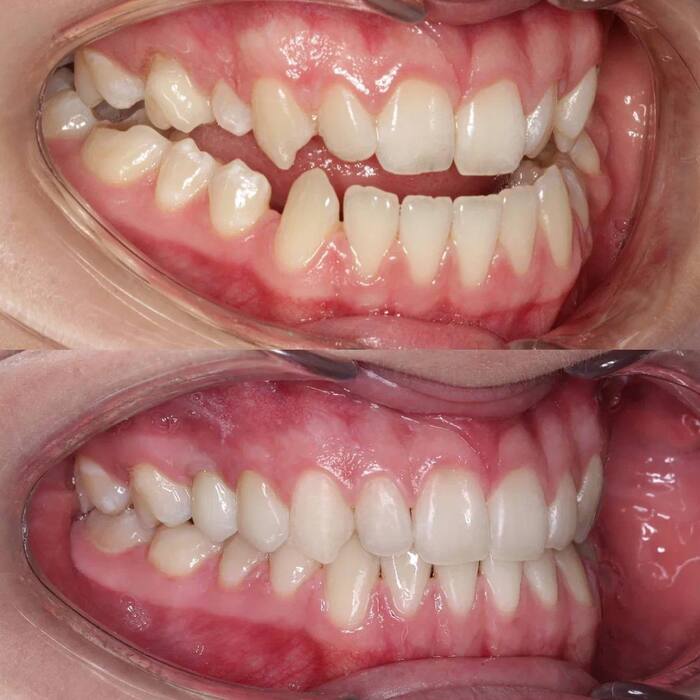

До или клиническая ситуация : нижние зубы перекрывают верхние (обратное перекрытие), наличие щелей между верхними и нижними зубами, несовпадение центров верхнего и нижнего зубных рядов, нарушение смыкания боковой группы зубов, кривизна резцов, практически полное отсутствие места для правого верхнего клыка.

Диагноз: мезиальный прикус, обратная резцовая окклюзия, трансверзальная резцовая окклюзия, дизокклюзия в области 1.3, 1.2, 2.2 и 2.3, перекрестная палатиноокклюзия в области боковой группы зубов, скученность и ретрузия резцов обеих челюстей.

Решение: дистализировать (смещать назад) весь нижний зубной ряд целиком с опорой на два ортодонтических винта для нормализации смыкания боковой группы зубов. Увеличить наклон резцов верхней челюсти до нормальных значений для получения правильного перекрытия резцов в сагиттальной и вертикальной плоскостях. Использовать раскрывающую пружину для раскрытия места под правый верхний клык и сопоставления косметических центров верхнего и нижнего зубных рядов между собой. Расширить верхний зубной ряд для коррекции перекрестного прикуса в боковых отделах и добычи пространства для правого верхнего клыка.

Результат: получили физиологический прикус, нормализовали смыкание фронтальной группы зубов во всех плоскостях (сагиттальной, вертикальной и трансверзальной). Добились правильного смыкания зубов в боковых отделах. Расширили зубные ряды и нормализовали наклон резцов верхней челюсти.